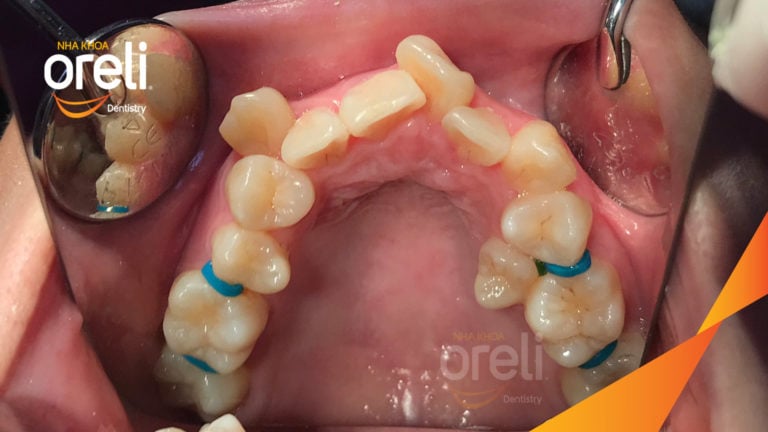

Ca niềng mắc cài tự khóa không nhổ răng – Kết quả sau 24 tháng tại nha khoa Oreli Niềng răngChen chúc Xem thêm